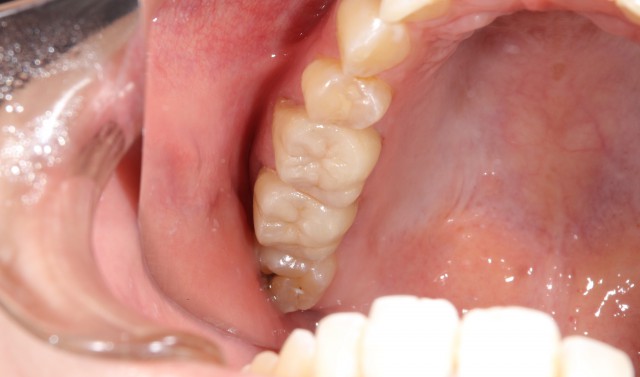

施術後

金属アレルギー対策はもちろんですが、口をあけたときにも金属が目立つということがないので非常に美しいです。口腔内の金属は歯ぎしりの原因となっているということもあります。たとえば髪が抜けやすくなった、肌にブツブツが出来やすいなどの症状などは金属アレルギーかも知れません。一度病院でアレルギー検査を行うことをおすすめします。